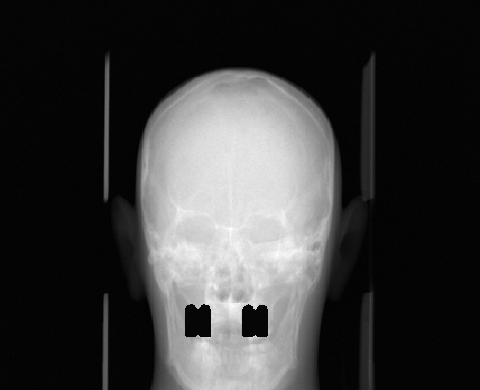

In practice, the complex wavelet transform is an effective tool for extracting singularities from a signal, as previously demonstrated for CT wavefront set extraction in [39]. In images and volumetric data, large-magnitude wavelet coefficients typically occur near jumps and edges. See Fig. 1 for an example of a sinogram containing two metal inserts, where the sum of the absolute values of the wavelet coefficients reveals the corresponding metal boundaries.

We propose a MAR method for projection-domain metal segmentation and inpainting, that uses 3D DT-CWT to find the edges of metals in the 3D sinogram. Fig. 2 shows the full workflow from 3D sinogram to metal artifact reduced reconstruction. The method is explained in detail below.

We computed the uncorrected FDK reconstruction, the image-domain hard-thresholding–based MAR reconstruction, and the proposed projection-domain complex wavelet MAR reconstruction for datasets (I–V). Fig. 4 shows selected slices from the reconstruction volumes for each dataset, displayed using identical windowing. The quantitative results of the metal segmentation are reported in Table 1 for datasets (I) and (II).

Dataset (I) contains three simulated titanium inserts in an otherwise homogeneous PMMA phantom. Consequently, metal segmentation in both the image and projection domain is expected to be relatively straightforward. As seen in Fig.4, the uncorrected FDK reconstruction exhibits substantial metal artifacts, which are particularly prominent in the axial slices. The HT-MAR method is able to reduce these artifacts to a large extent. However, residual artifacts remain near the metal boundaries as a result of imperfect segmentation. Even after morphological widening of the image-domain segmentation, the mask remains too narrow in some regions while being overly wide in others. This behavior is evidenced by the close-up reconstruction images and the segmentation metrics reported in Table 1. In contrast, the proposed CW-MAR method yields a more accurate projection-domain segmentation, resulting in an almost complete suppression of metal artifacts due to the tighter and more consistent segmentation.

Dataset (II) presents a considerably more challenging MAR problem, featuring eight metal implants in a more complex anthropomorphic phantom. The uncorrected FDK reconstruction is again heavily affected by metal artifacts, which are prevalent in all slicing directions and obscure many anatomical structures. The HT-MAR method is able to reduce these artifacts to a reasonable extent, with projection inpainting restoring much of the missing information. However, the estimated metal boundaries are somewhat inaccurate and include portions of bright artifact regions. The CW-MAR method captures the metal boundaries more robustly. Nevertheless, some room for improvement remains, as projection inpainting introduces mild blurring in the vicinity of the metal regions.

First of the experimental metal datasets, dataset (III) provides a simple test case for severe artifacts caused by an amalgam filling. As in dataset (I), the HT-MAR approach reduces artifacts in the uncorrected FDK reconstruction. However, residual artifacts persist due to missed metal voxels near the metal boundaries in the segmentation. The CW-MAR method removes nearly all artifacts, particularly in the sagittal and coronal slices.

Dataset (IV) produces substantial artifacts in the FDK reconstruction. For HT-MAR, identifying a suitable threshold level is challenging, as the HU values of the artifacts overlap with those of the actual metal features. This leads to poor metal segmentation. In contrast, CW-MAR removes most artifacts and recovers the general shape of the prosthesis.

Dataset (V) presents a particularly challenging MAR scenario, in which the metal object is partially outside the reconstruction field of view (FOV). As a result, streaking artifacts are present even when the metal itself does not appear within the reconstructed volume. The large screw produces severe artifacts in the uncorrected FDK reconstruction. The image-domain HT-MAR approach is unable to reduce artifacts caused by metals outside the reconstruction FOV and additionally struggles with accurate boundary segmentation, especially in the coronal direction, where the screw geometry is particularly challenging. In contrast, the CW-MAR method is not affected by metals outside the reconstruction FOV, since segmentation is performed in the 3D sinogram domain, where the corresponding metal trace is present. Consequently, artifact reduction is effective. However, as in previous cases, projection inpainting introduces some blurring, which in this dataset leads to a loss of fine anatomical detail.